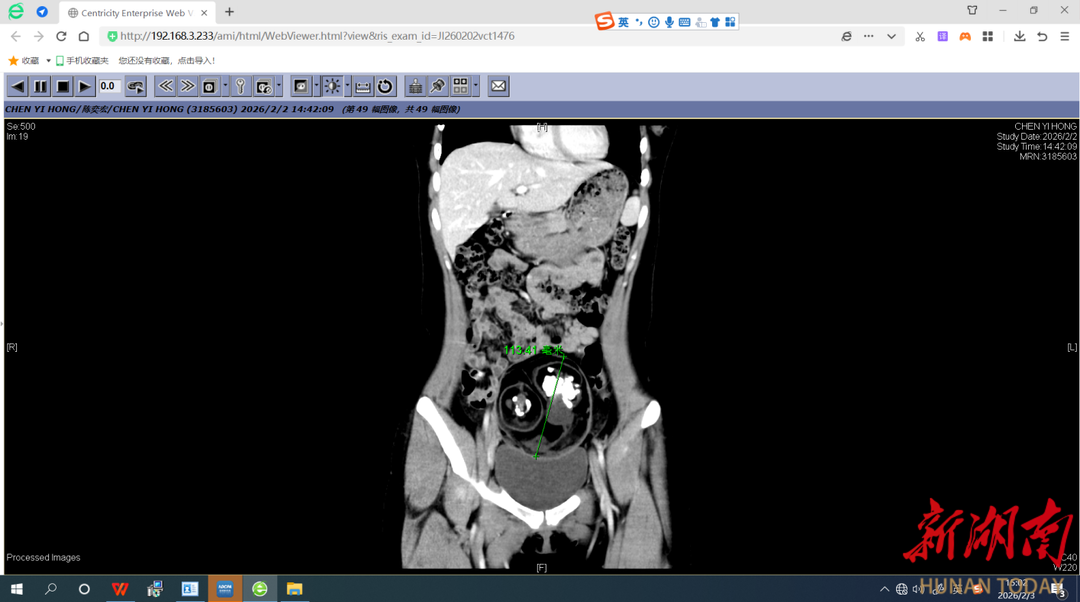

CT检查示下腹部有一直径约12厘米的肿块 术中清理出来的肿瘤内容物(含牙齿、骨骼)

湖南日报·新湖南客户端3月16日讯(通讯员 魏馨 朱文青)近日,18岁的曾琳琳(化名)在家跳操时突然出现右下腹持续性剧烈疼痛,立即前往长沙市中心医院(南华大学附属长沙中心医院)妇科就诊,彩超报告显示,她的下腹部藏着一个直径达12厘米的巨大肿块,更令人震惊的是,肿块内部疑似有牙齿和骨骼的影像!

一听说要手术,年仅18岁的曾琳琳非常恐惧,她担心手术的疼痛,也害怕腹部会留下明显的疤痕影响美观。面对琳琳的担忧,魏馨和团队经过充分的术前评估与讨论,为她量身定制了“经脐单孔腹腔镜手术”的治疗方案。手术由魏馨主刀,凭借精湛的技术和丰富的经验,团队通过这唯一的肚脐切口,成功将直径12厘米的畸胎瘤完整无损地剥离并取出。术后清点肿瘤内容物时,连医护人员都感到惊讶:里面竟然包含了24颗形态各异的牙齿,以及最大直径接近5厘米的骨骼组织。